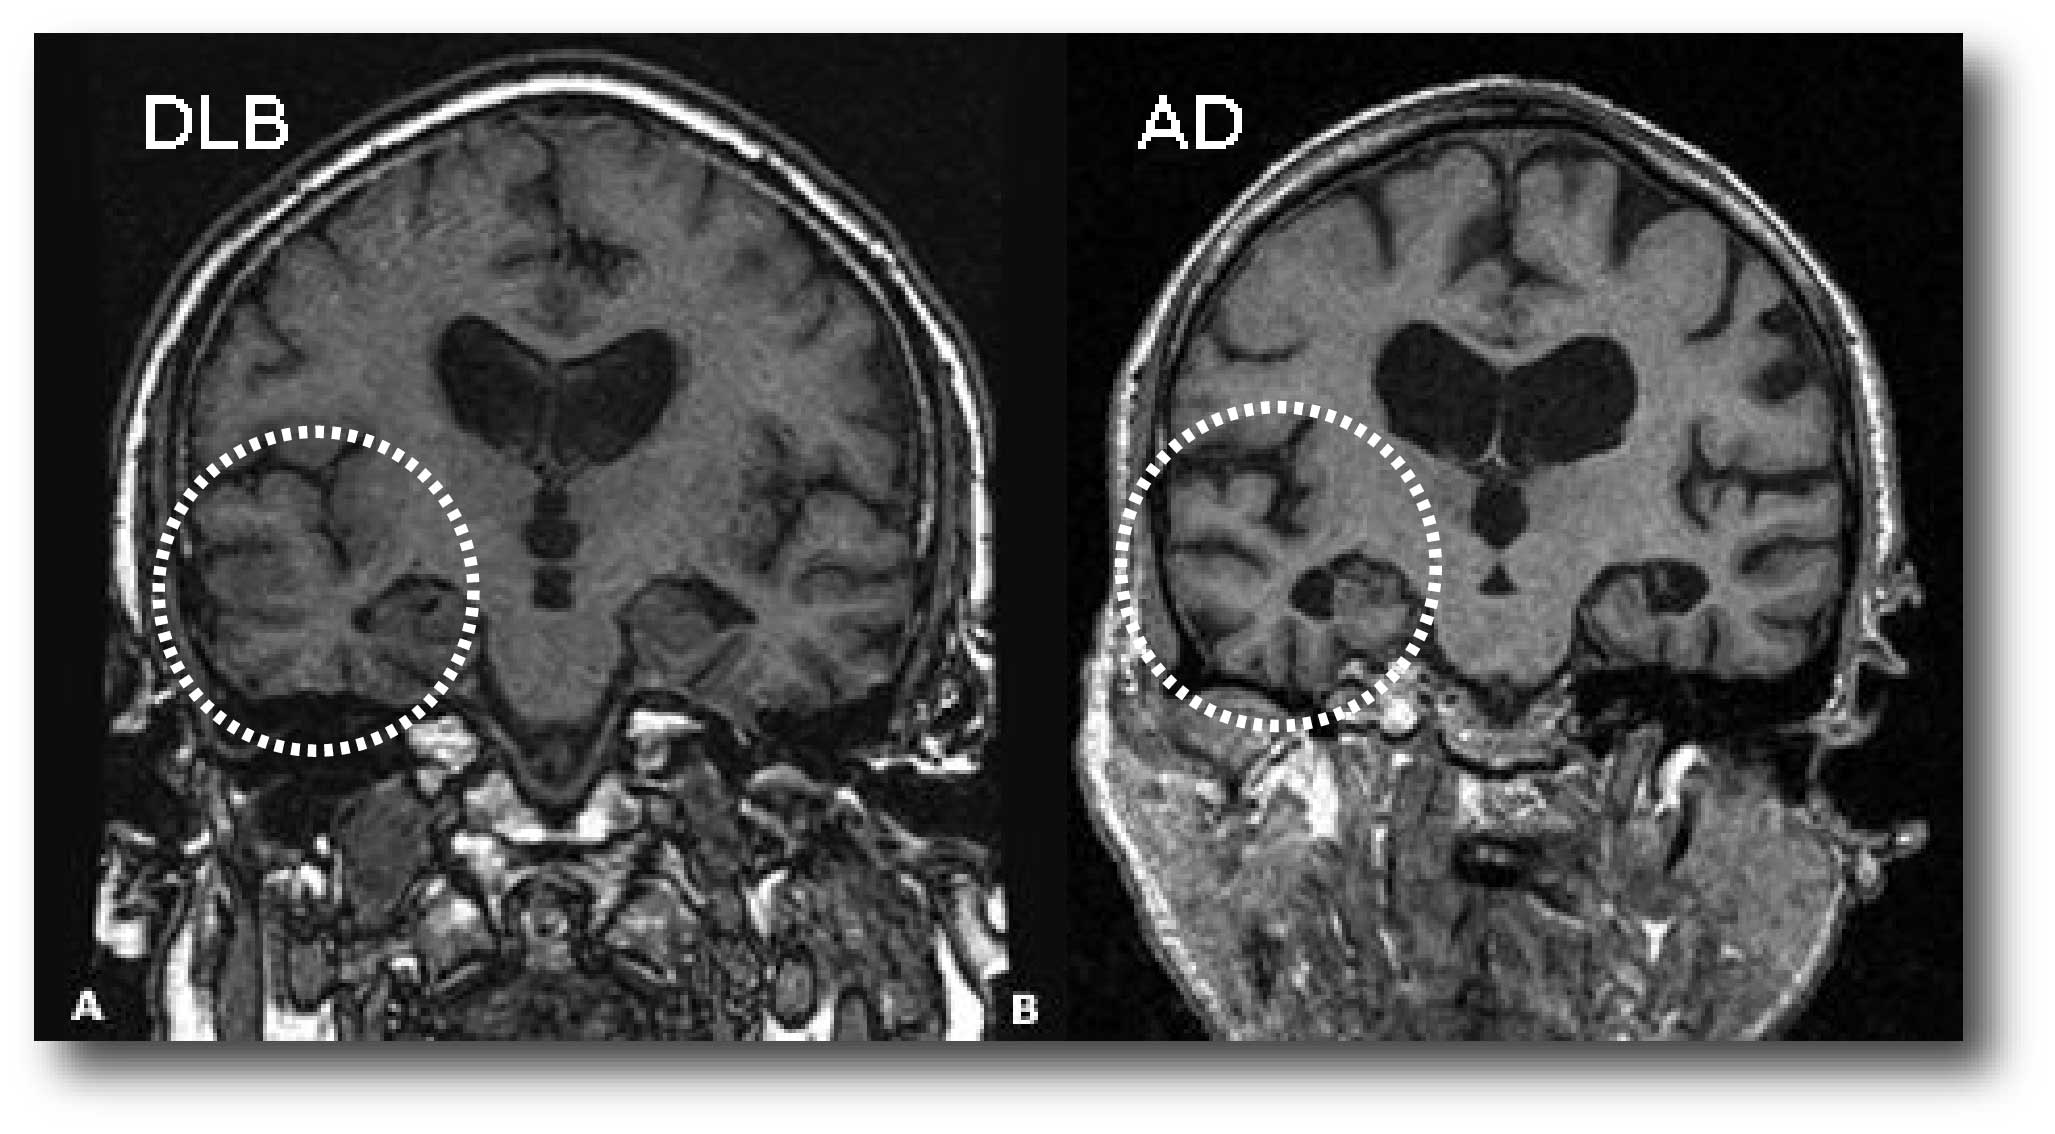

- Relative preservation of medial temporal lobe structures on brain scans (CT/MRI) – people with Alzheimer’s disease show greater shrinkage of medial temporal lobe structures of the brain than people with Dementia with Lewy bodies. In the image below you can see a CT brain scan from a 61-year-old man with Dementia with Lewy bodies (DLB) and a 69-year-old male with Alzheimer disease (AD). Note the lack of shrinkage of the medial temporal lobes in the circled area in panel A when compared to panel B.

Temporal lobe size in a brain scan. Source: Cursoenarm